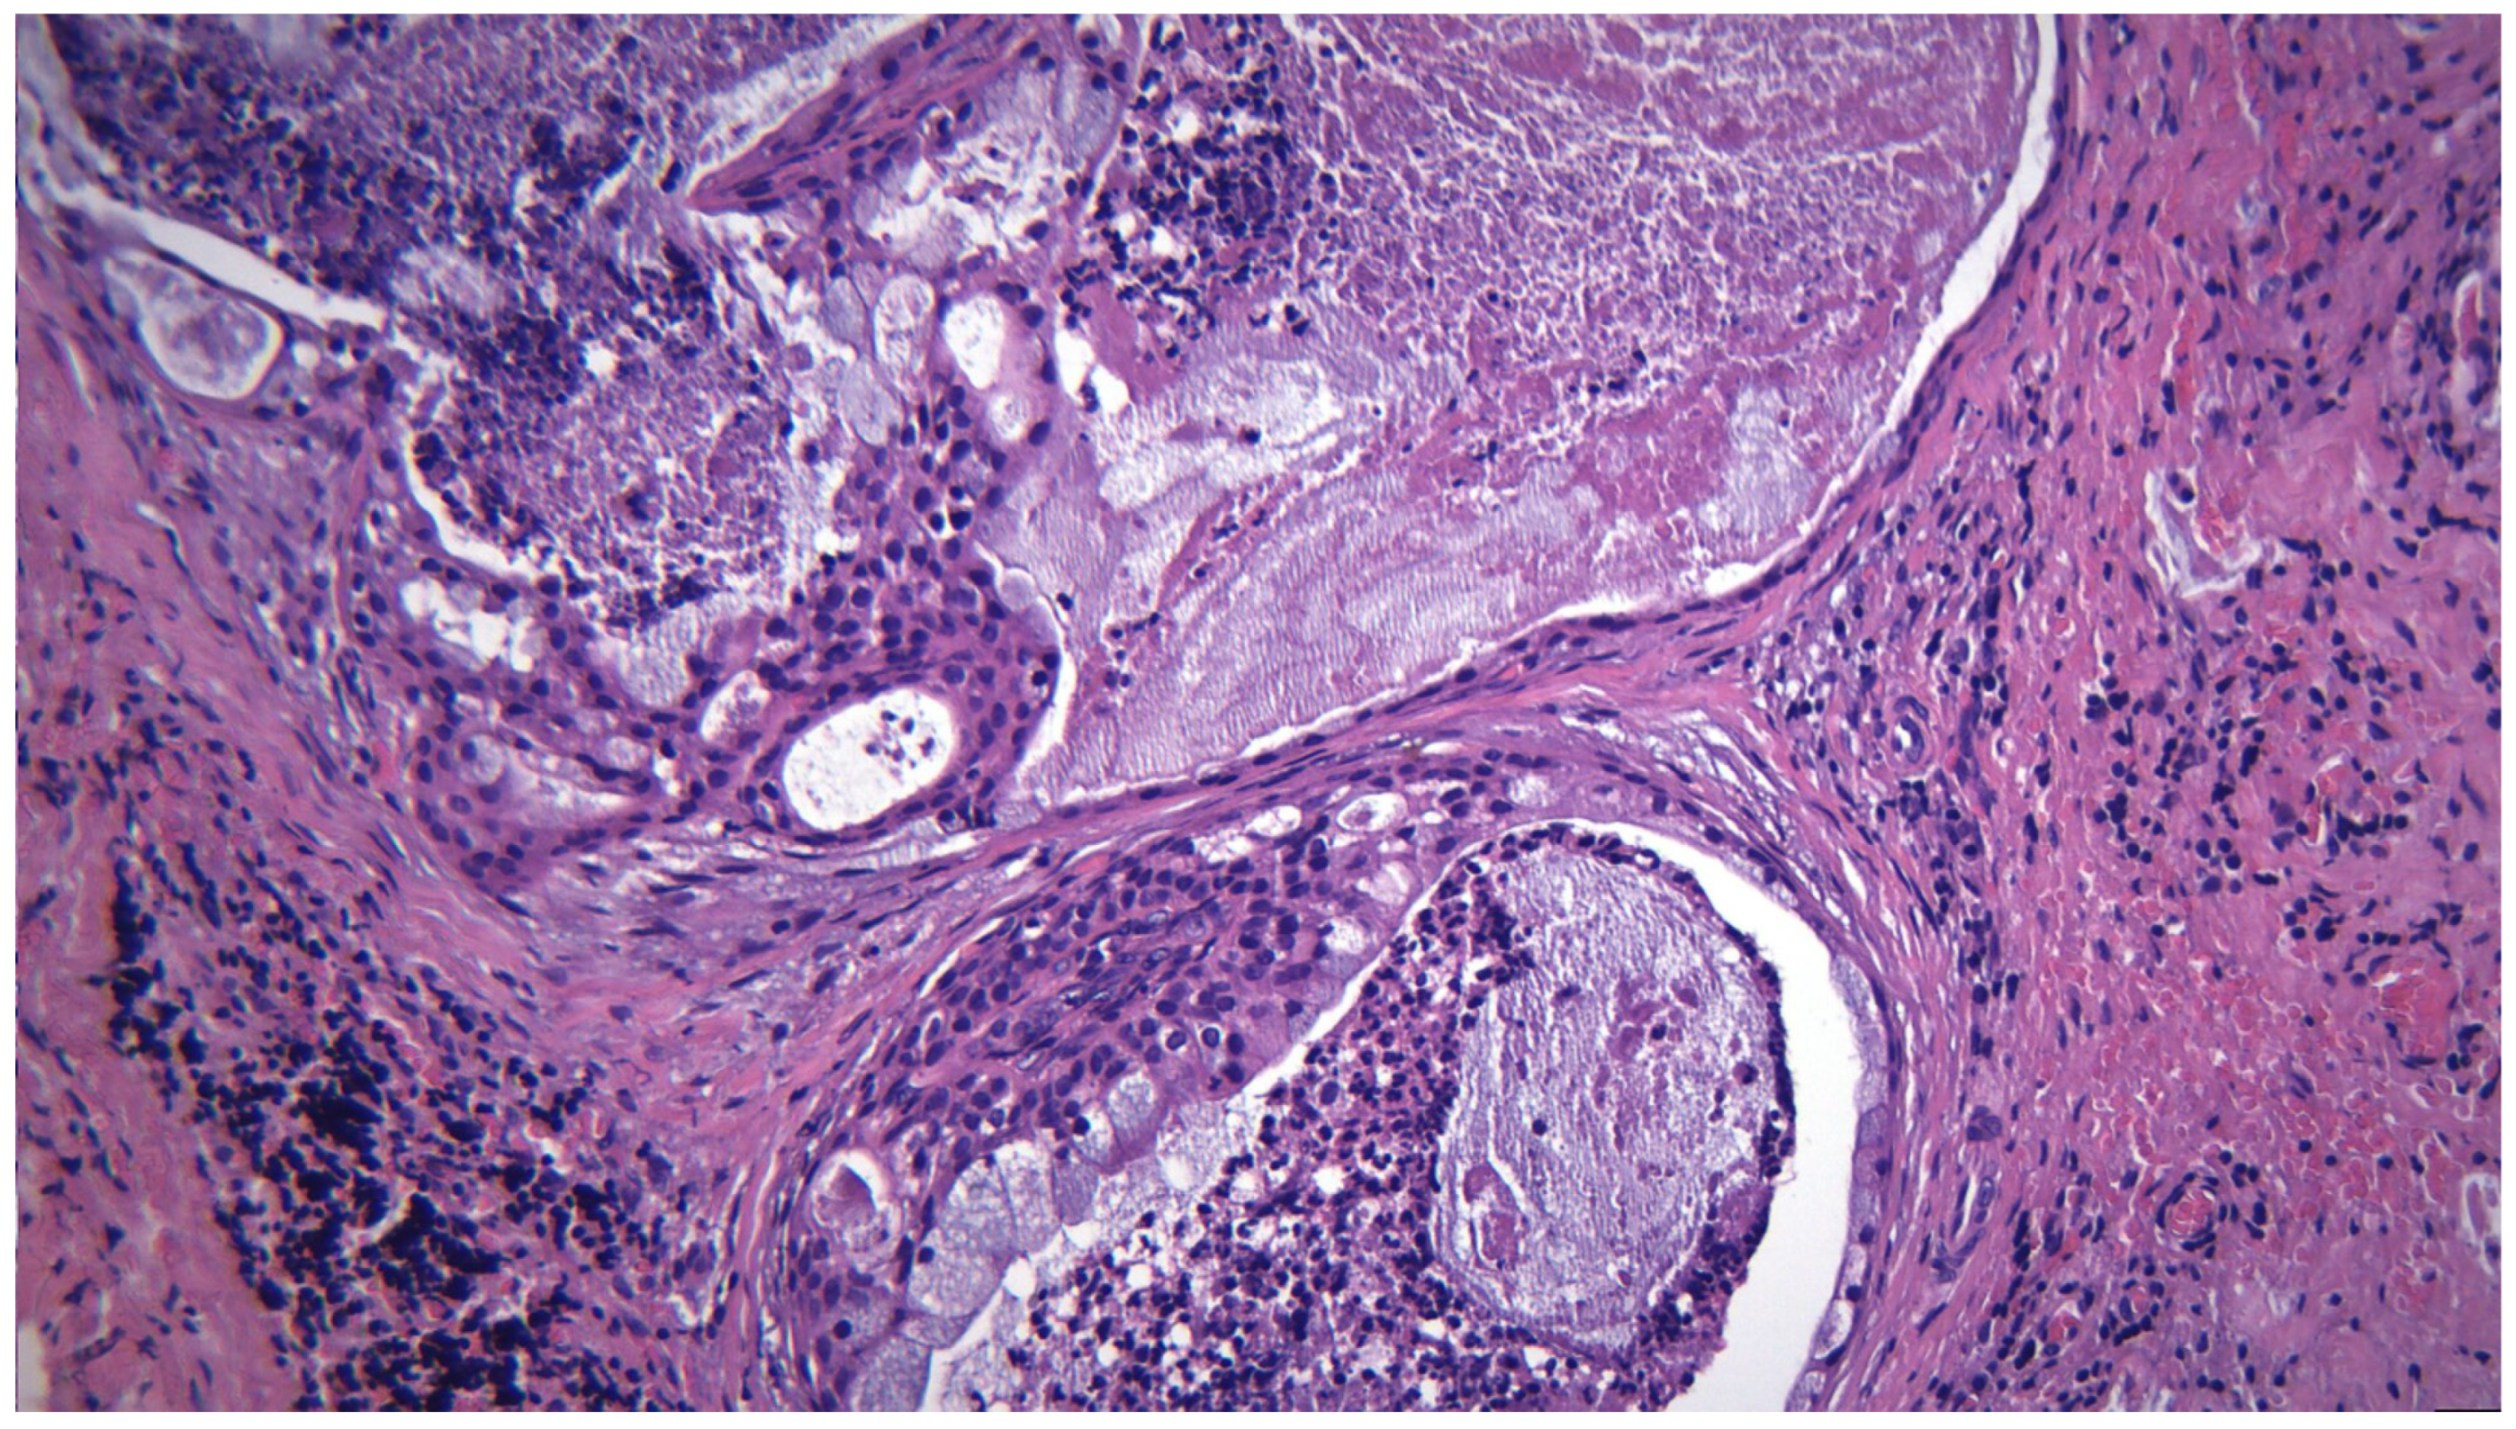

3.14. Mucoepidermoid Carcinoma